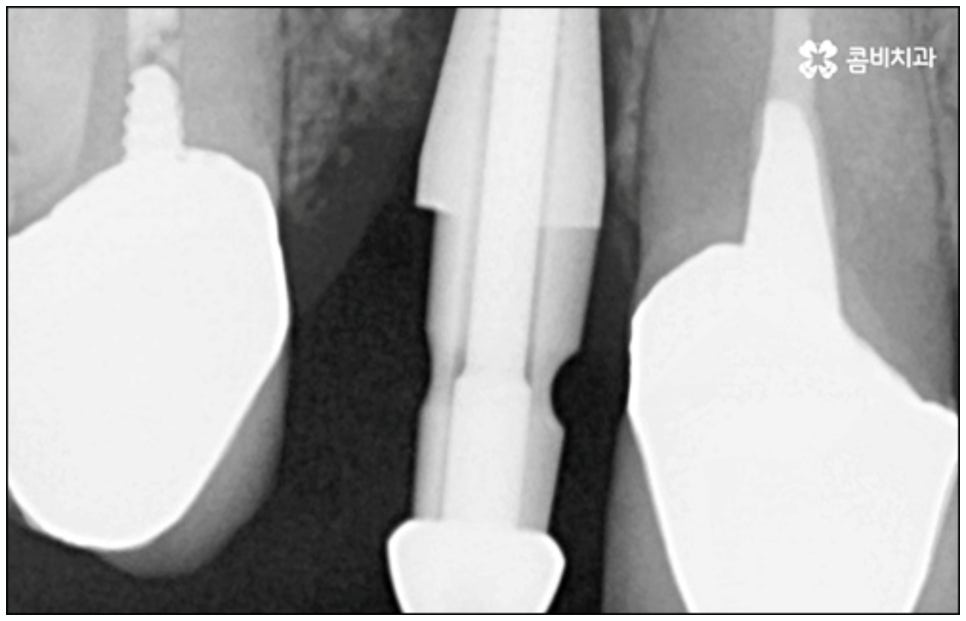

하지만 근래 치의학이 점점 더 발달하고 임플란트 관련 기술이 진일보하면서, 발치한 당일 인공치근을 심고 임시 치아까지 장착하여 바로 씹을 수 있도록 한 당일임플란트 방법이 개발되어 전체 치료 기간을 대폭 줄일 수 있는 가능성이 높아지면서 이에 대한 문의가 많아지고 있어요. 과거에는 보통 발치 후 2~3개월 정도 기다려서 잇몸뼈가 어느 정도 회복된 다음 잇몸을 절개하고 임플란트를 식립하는 방식으로 진행을 했었다면 당일임플란트 방식은 인공 치근 주변 남는 빈 공간을 뼈이식술을 통해 바로 보강, 이후 잇몸뼈가 자연스럽게 아무는 과정에서 좀 더 빠르게 골융합이 이루어지도록 돕기 때문에 일반 임플란트 방식에 비해 기간을 단축시켜 줄 수 있는 거예요.

또한 발치 즉시 식립을 진행하게 되면 치아 상실 후 해당 부위를 오래 방치하지 않아도 되기 때문에 잇몸뼈를 가능한 그대로 유지 보존할 수 있어 수복시 보다 자연스러운 잇몸라인 형성을 기대할 수 있으며 한 번의 마취로 발치 및 식립을 한꺼번에 진행할 수 있어 환자분들의 입장에서 기간 단축 뿐 아니라 자주 치과에 내원해야 하는 불편함 및 통증에 대한 두려움을 덜 수 있다는 장점이 있어요.

이때 당일임플란트 시술은 정밀함을 요하는 고난도 치료에 속하는 만큼 의료진의 숙련도에 영향을 많이 받기 때문에 안정적으로 골이식재가 자리잡고 식립된 임플란트가 보다 오랜 기간 강한 저작력을 견딜 수 있도록 지속력을 높이기 위해서는 다양한 환자분들의 임상 치료 경험과 뛰어난 노하우, 정확한 판단력 및 세심한 실력을 갖춘 의료진에게 시술을 받으실 필요가 있습니다.

또한 한 번 식립된 인공 치근이 뼈조직과 골융합되고 난 다음에는 그 위치와 방향을 수정하기 어려운 만큼 혹시 모를 부작용이나 재수술 위험 없이 임플란트 치아를 사용할 수 있도록 안정성이 검증된 정품 재료를 사용하고 있는지, 잇몸 상태와 구강 구조를 세밀하게 체크할 수 있는 3D CT와 같은 정밀 검진 장비를 활용하는지 등등을 함께 꼼꼼하게 체크해 볼 필요가 있어요. 그리고 언급했던 것처럼 사후 관리 역시 임플란트 수명에 큰 영향을 주니 철저한 케어 시스템을 갖추고 임플란트 유지 관리를 도와주는 치과에서 진행하는 것 역시 중요하다고 할 수 있습니다.